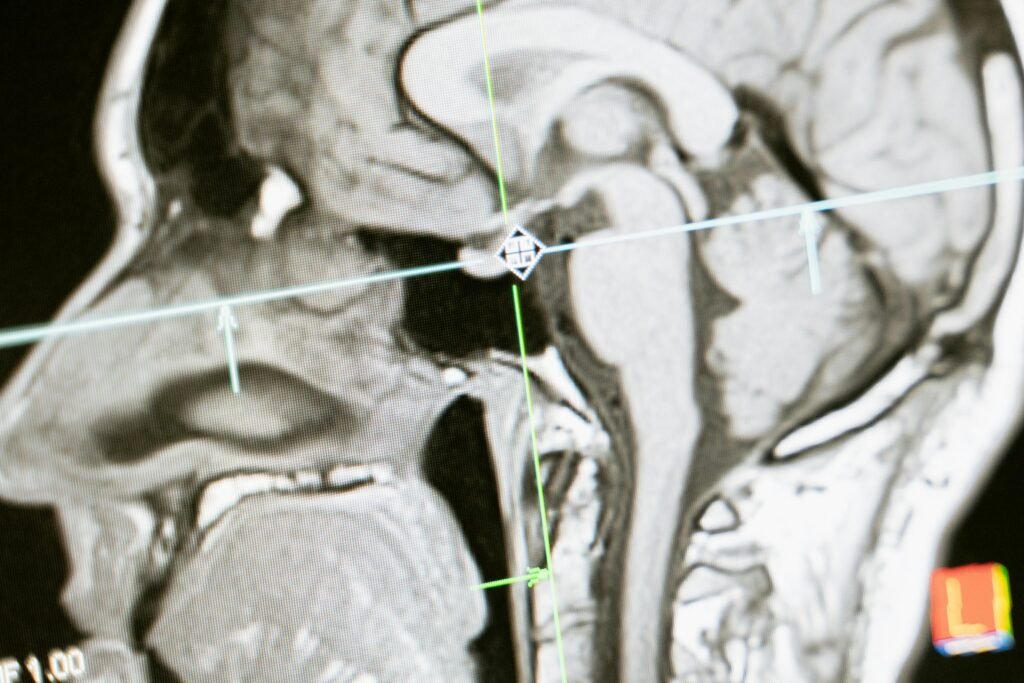

Close-up of an MRI scan showing a sagittal view of the human brain for analysis.

Pituitary Issues

we also treat disorders of the pituitary gland such as prolactin issues, pituitary tumors called adenomas